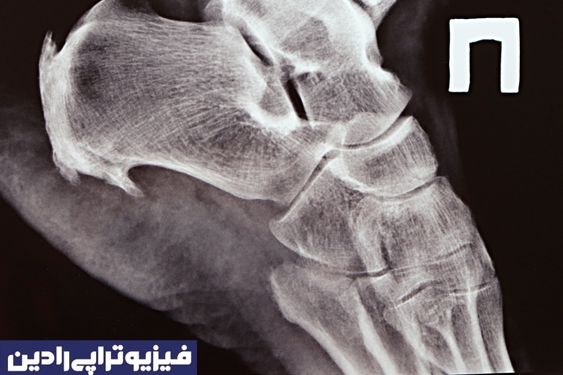

بعضی مواقع این امکان وجود دارد که این عارضه از زیر پاشنه تا قوس پا گسترش پیدا کند که به این ناحیه «فاسیای کف پا» گفته میشود. زمانی که خار پاشنه در اشعه ایکس دیده میشود، ممکن است طول آن تا یک و نیم سانتی متر برسد.